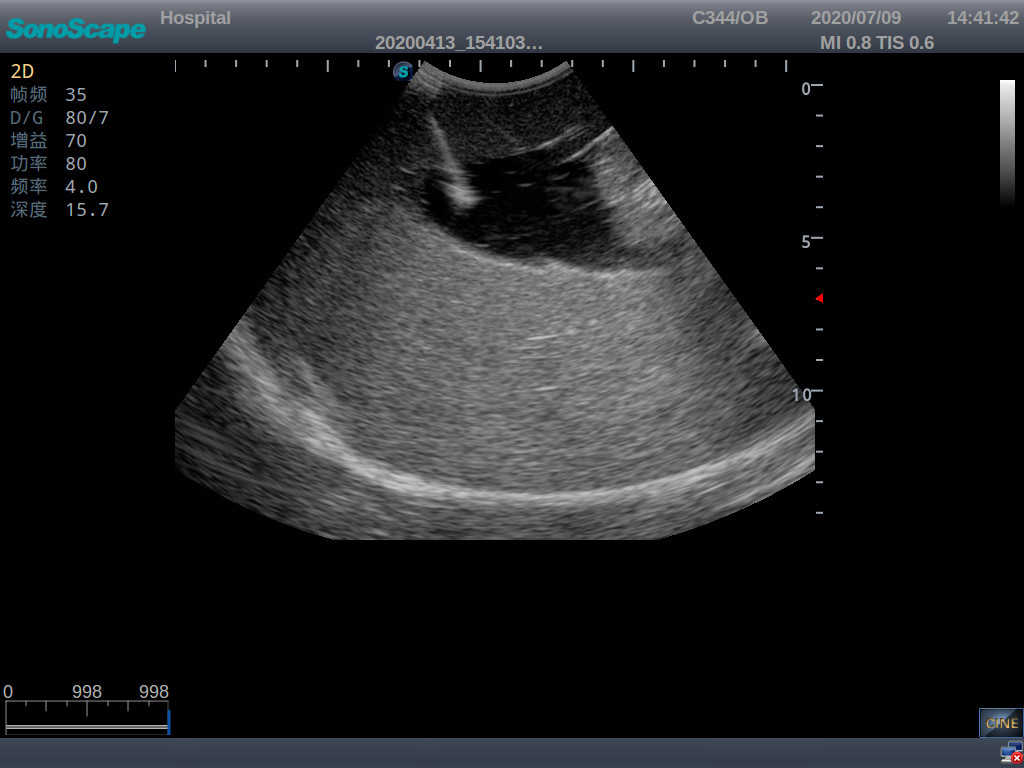

· High-quality ultrasound images for users to recognize 22-week fetus, placenta, placenta, umbilical cord and amniotic fluid